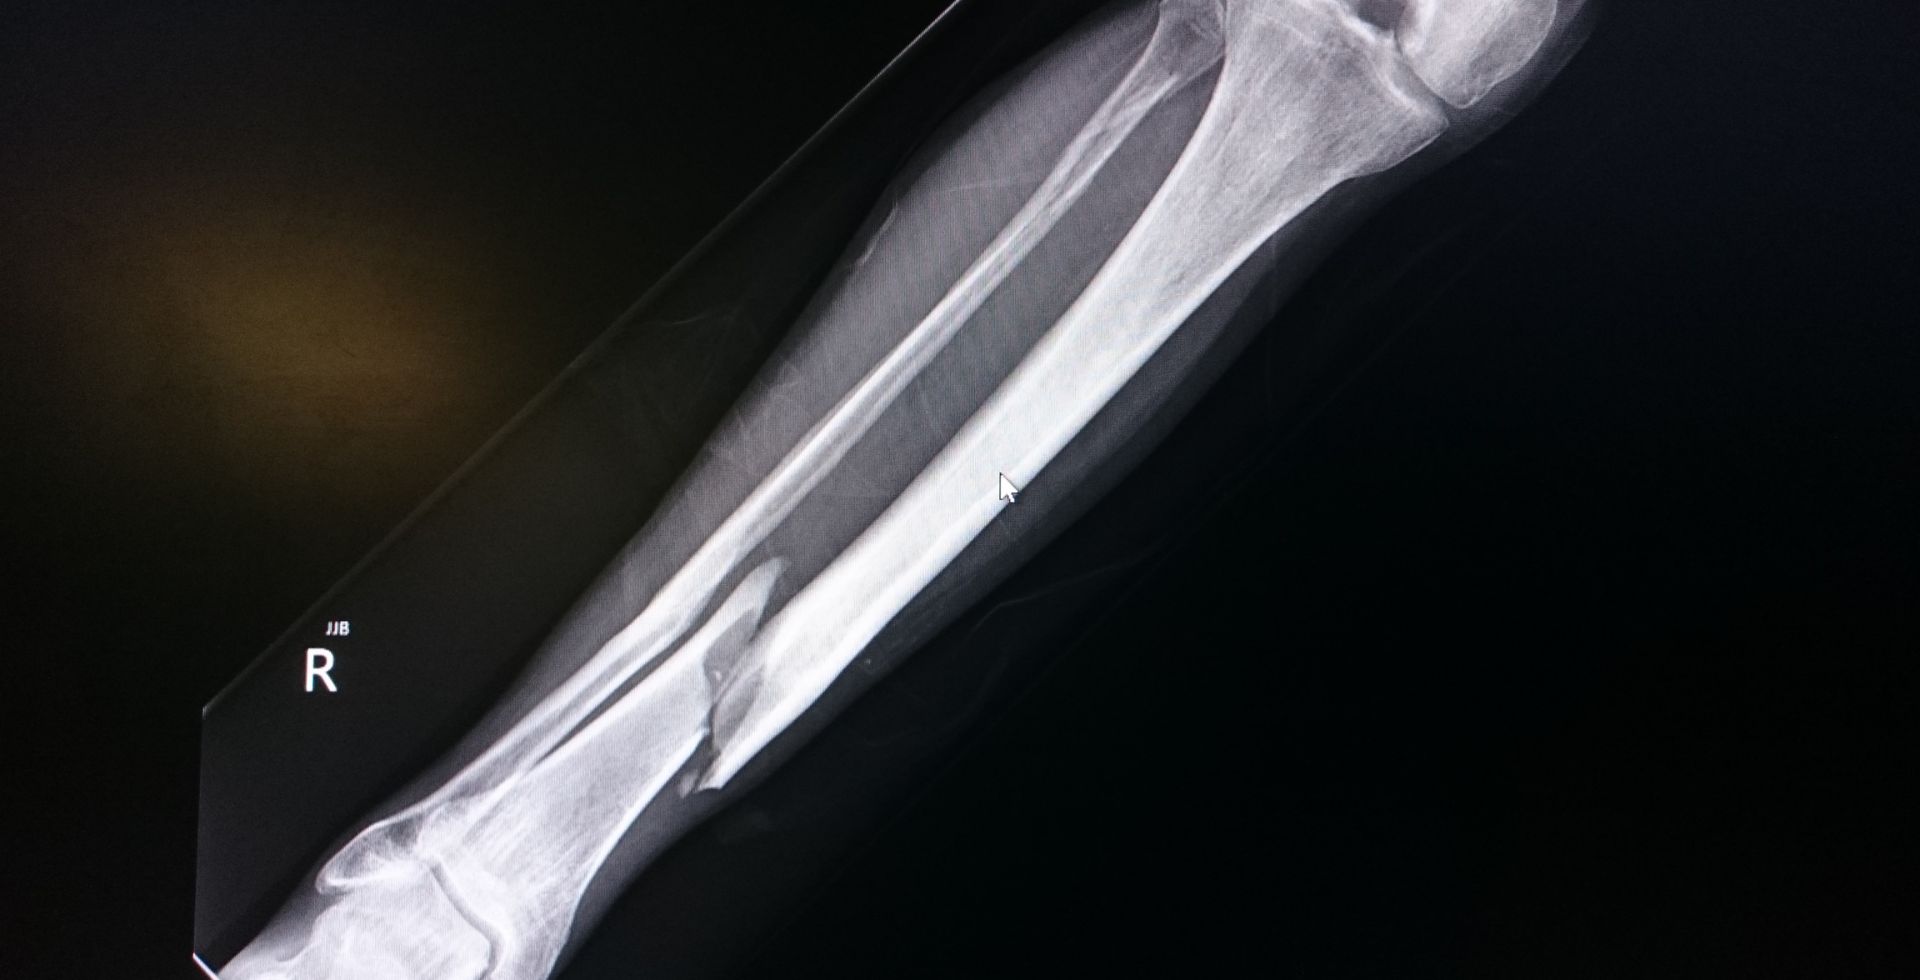

Fracture surgeries involve surgical procedures to repair broken bones. These surgeries are necessary when fractures are complex, displaced, or fail to heal properly with conservative treatments. The primary goal is to realign and stabilize the bone, promote healing, and restore function.

Fracture surgeries are considered when there are severe breaks, multiple fractures, or when bones are misaligned. These surgeries can help reduce pain, prevent complications, and ensure proper healing, allowing patients to return to their daily activities with minimal disruption.

• Open Reduction and Internal Fixation (ORIF)

• External Fixation

• Intramedullary Nailing

• Bone Grafting